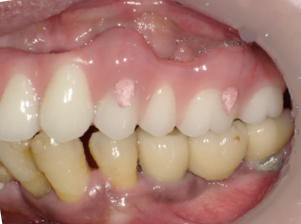

前歯に連結固定した差し歯が入っています。おそらく奥歯がなりなり、噛めなくなるので、前歯でしっかり噛めるように連結固定したのだと思いますが・・

治療前の写真です。前歯がぐらぐらになっています

奥歯がなくなり、前歯ばかりで噛んでいるとフレアーアウトといって前歯がどんどん前に傾いて出てきます。